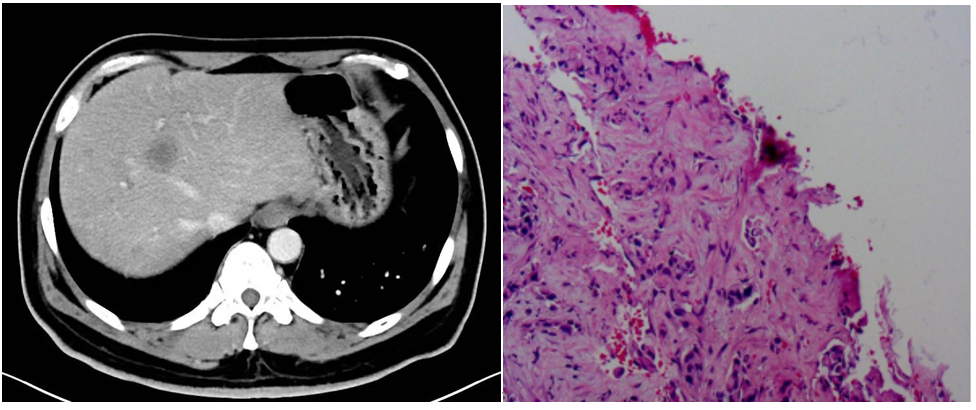

靶向治疗虽然效果显著,但耐药问题常见。本例患者在治疗7个月后出现耐药,肿瘤发生肝和骨髓转移。给予患者肝穿刺再活检明确耐药机制。后患者出现不明原因出血,实验室检查血小板、血红蛋白和纤维蛋白原进行性下降。唐晓勇主任及时与患者就诊的山东第一医科大学第二附属医院刘海燕主任团队沟通,最后考虑为肿瘤进展引起的DIC纤溶亢进。患者生命垂危!就在这千钧一发的时刻,基因检测结果回示ALK和RET双融合突变,立即给予针对洛拉替尼和塞普替尼双靶药物联合治疗,2天后患者症状明显好转,5天后血检结果恢复正常患者出院。